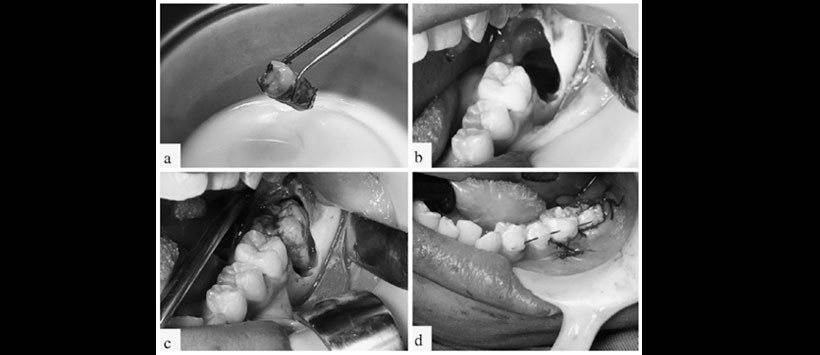

Figura 4: Autotransplante. Diente donante almacenada en leche pasteurizada (a), Lecho alveolar preparado para la recepción del diente donante (b), Pieza 3.8 en su posición definitiva (c), estabilización de la pieza donante mediante ferulización (d).